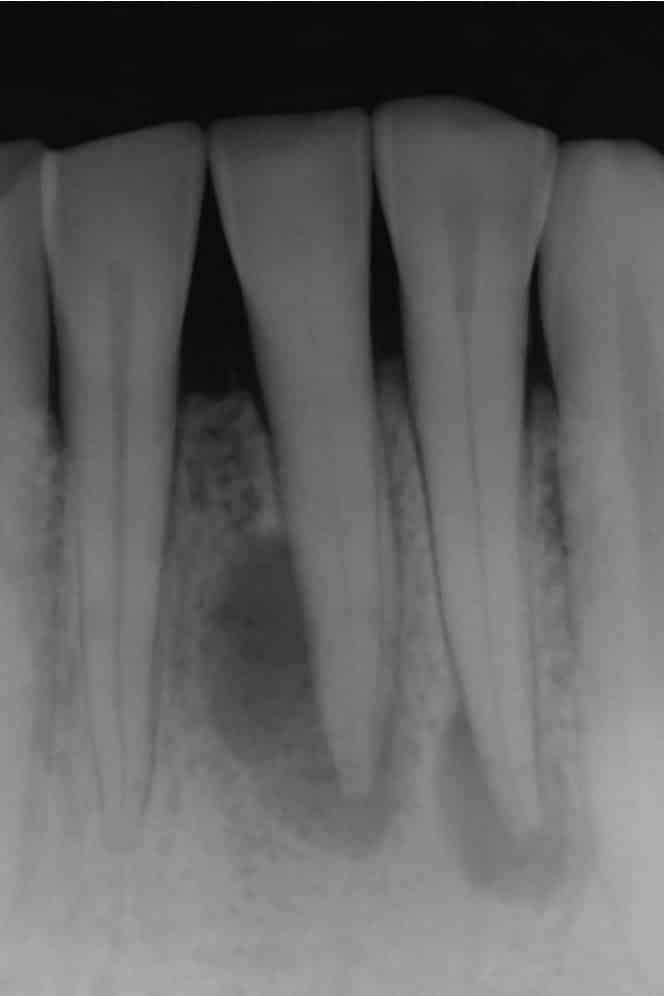

Изображение рентгенограммы зубов с кистозными образованиями (темные участки с четкими границами рядом с корнями)

На любом этапе заболевания наиболее точный диагноз можно установить с помощью рентгенографии. Она позволяет увидеть наличие капсулы как на начальной, так и на конечной стадиях.

2. Рентгенография

Рентгенография является одним из основных методов диагностики кисты зуба. На рентгеновских снимках киста выглядит как затемненное образование вокруг корня зуба. Этот метод позволяет не только подтвердить наличие кисты, но и оценить ее размер, форму и расположение относительно соседних зубов и тканей. В некоторых случаях может потребоваться использование панорамной рентгенографии для более детального анализа.